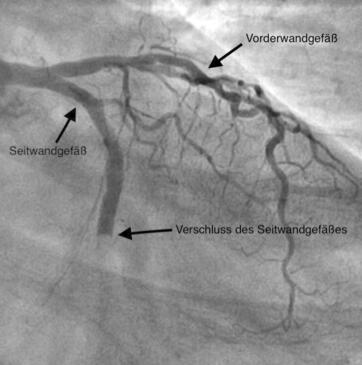

Die Koronarangiographie (Darstellung des Herzkranzgefäßes mittels Röntgenkontrastmittels) führt zum Nachweis von Einengungen, Verkalkungen und Verschlüssen der Herzkranzgefäße. Sie ist eine wichtige Voraussetzung, um zu entscheiden, ob eine medikamentöse Therapie, eine Ballonaufdehnung (PTCA) oder eine Bypassoperation sinnvoll ist. Im Falle einer Einengung des Herzkranzgefäßes kann diese in der gleichen Sitzung mit Ballonaufdehnung (PTCA/PCI) und Stent (Gefäßstütze) behandelt werden.

Wird im Rahmen der Herzkatheteruntersuchung eine Verengung eines

oder mehrere Gefäße festgestellt, jedoch ohne dass der

Schweregrad der Koronarstenose angiographisch eindeutig abzuschätzen ist und somit

den Blutfluss eindeutig beeinträchtigen würde, wird die Messung der

Fraktionierten Fluss Reserve durchgeführt.